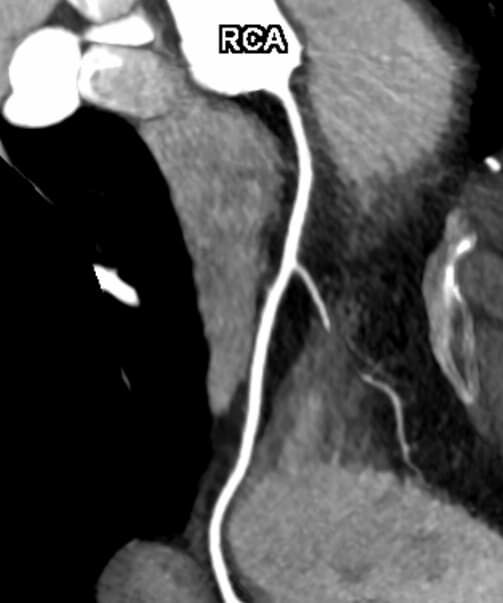

• Darstellung der Blutgefäße (sog. CT- Angiographie)

Thorax (Brustkorb)

• Entzündungen oder Tumore des Mediastinums und der Lunge

• Lungenembolie- Diagnostik

• hochauflösende Darstellung des Lungenparenchyms zur Abklärung chronischer interstitieller Erkrankungen wie z. B. Fibrosen, Emphysem, Bronchiektasen

Herz

• mehrdimensionale Darstellung vasculärer Strukturen mit zahlreichen Auswertungstools